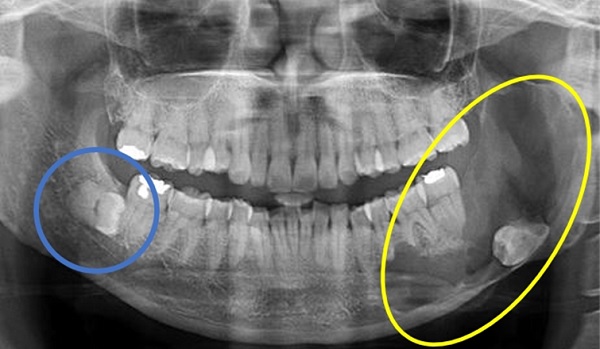

치과 치료를 하면 알 수 있는 것이 치아는 함부로 뽑지 않습니다. 정말 최대한 살려보고 그래도 안 되면 뽑아서 임플란트 등으로 빈자리를 채웁니다. 사랑니는 다른 치아들과 달리 발치를 해야 할 때도 있습니다. 잘 자란 사랑니는 특별한 문제를 일으키지 않아 뽑지 않아도 됩니다. 하지만 대부분의 사랑니는 말썽을 부립니다. 출혈, 염증, 통증 및 악취, 충치 들 여러 가지 문제를 일으킬 확률이 높기 때문에 뽑아야 합니다.